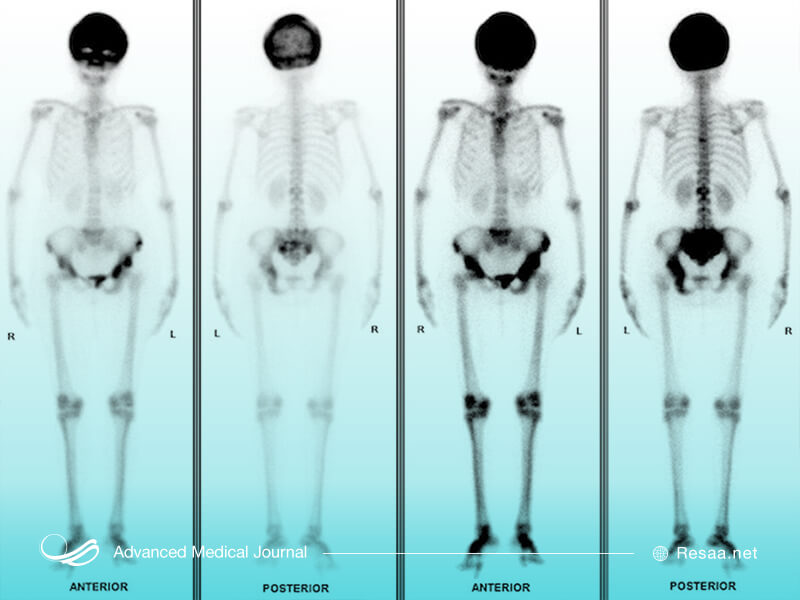

بعضی اوقات پزشک، اسکن استخوان ایزوتوپ “isotope” که مؤثرترین روش برای مشخص کردن محل قرارگیری استخوان تحت تأثیر بیماری است را تجویز میکند، تا متوجه شود چه مقدار از استخوانها تحت تأثیر قرار گرفته و چقدر فعال است. یک دوز کوچک و قابل تحمل ایزوتوپ رادیواکتیو (جهت تشخیص بیماری در اسکن استخوان) به رگ شما تزریق میشود و چند ساعت بعد، کل اسکلت شما اسکن میگردد. میزان کمی رادیواکتیو تزریق میگردد تا به بدن شما آسیب نرساند. ایزوتوپ در نواحی استخوانی متاثر از بیماری پاژه متمرکز میشود به طوری که با یک دوربین مخصوص، هنگام اسکن از بدن به طور واضح ظاهر میگردد. ماده رادیواکتیو، پس از اسکن و از طریق ادرار، به سرعت از بدن شما خارج میشود.